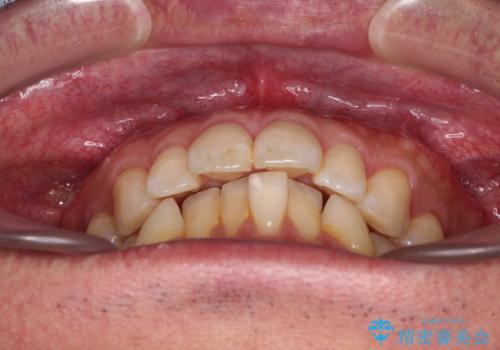

- 口元の突出感を気にして来院された患者様です。

強い咬合力と上顎前歯の傾斜により前歯が突出し、唇が閉じにくい状況であったため、上下左右の第一小臼歯4本を抜歯し、ワイヤー装置にて矯正治療を行うこととしました。

非常に咬合力が強いため、抜歯したスペースが閉じるのか不安でしたが、順調に歯が移動し、予定よりも早く治療を終えることができました。